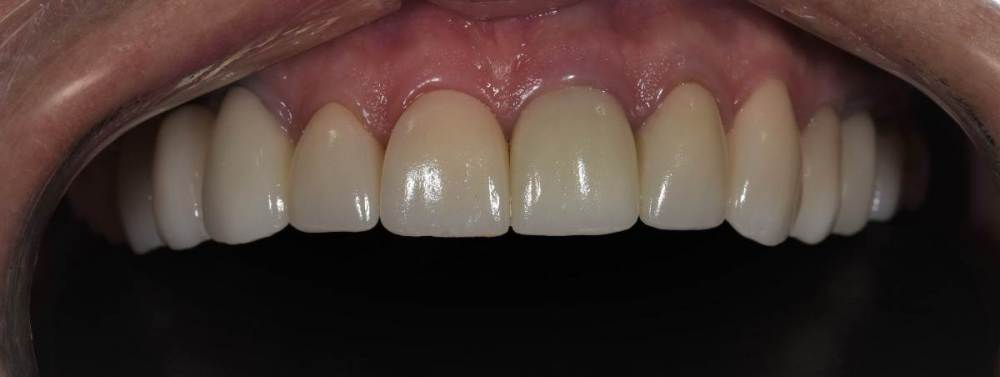

Финал работы:

DSC_3144.thumb.JPG.c9e60b8847f66dc01ba0e6e1113ab39b.JPGDSC_3145.thumb.JPG.1723748a079bc482f1a7e4534aff8f33.JPGDSC_3146.thumb.JPG.6dd4d0eb29dc3e6e92773c3c7892f692.JPGDSC_3147.thumb.JPG.e4f9cc2d841e3b7ff3aa73491ba9b4a3.JPGDSC_3148.thumb.JPG.0f174600adf2a49d65266a0ff665abfd.JPGDSC_3149.thumb.JPG.c9849be795d45b2573488d4545f3843f.JPGDSC_3150.thumb.JPG.6380366ecde7802fa32c6471b8b33883.JPGDSC_3153.thumb.JPG.1420d109d08ed1d6bd63447fe73eeed6.JPGDSC_3154.thumb.JPG.04b902149b3c0f9f2f1bcfa2e310c855.JPG

Фото спустя месяц после фиксации. Сначала нижняя челюсть, потом верхняя. Решение с передними нижними зубами - компромиссное. Все они витальные, имели 2-3 степень подвижности. После исправления положения нижней челюсти и установления правильных окклюзионных контактов - 1-2 степень подвижности. По поводу гигиены пытаемся.